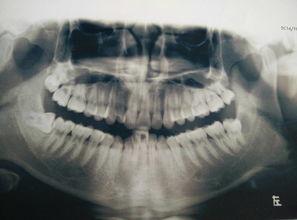

(2)根據(jù)牙在骨內(nèi)的深度分為:高、中、低位。 (3)根據(jù)阻生牙的長(zhǎng)軸與第二磨牙的長(zhǎng)軸關(guān)系可分為七類(lèi)阻生(見(jiàn)統(tǒng)編教材第三版) 4、術(shù)前檢查 (1)口外檢查:頰部腫脹,頜下淋巴結(jié),下唇麻木 (2)口內(nèi)檢查:張口,萌出及周?chē)装Y情況,第二磨牙、第一磨牙情況,全口牙、粘膜情況。

(3)X線攝片檢查:阻生牙萌出情況、牙根情況(數(shù)目、彎曲、分叉情況等)、第二磨牙情況:齲壞、牙周骨質(zhì)與阻生智齒的緊密程度等,與下頜管的關(guān)系。 5、阻力分析及拔除方法阻力分析及拔除法 (1)軟組織阻力-切開(kāi)翻瓣法 (2)冠部骨阻力-去骨法 (3)根部骨阻力-劈開(kāi)與去骨法相結(jié)合 (4)鄰牙阻力-劈開(kāi)與去骨法相結(jié)合各種拔牙方法及要求 (1)切開(kāi)翻瓣法: 目的:解除軟組織阻力、顯露手。